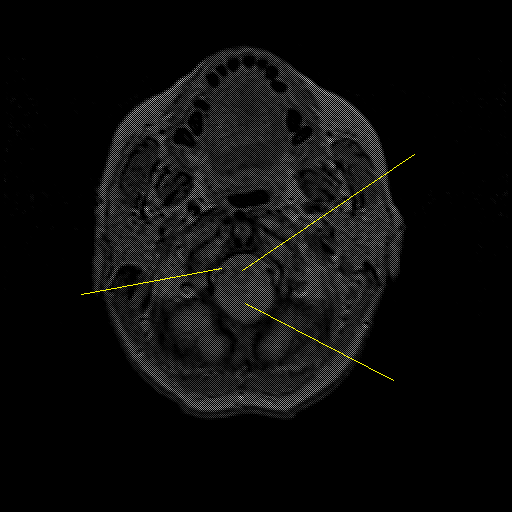

overlay : Slice 4

Slice 4

Pointers

Labeled